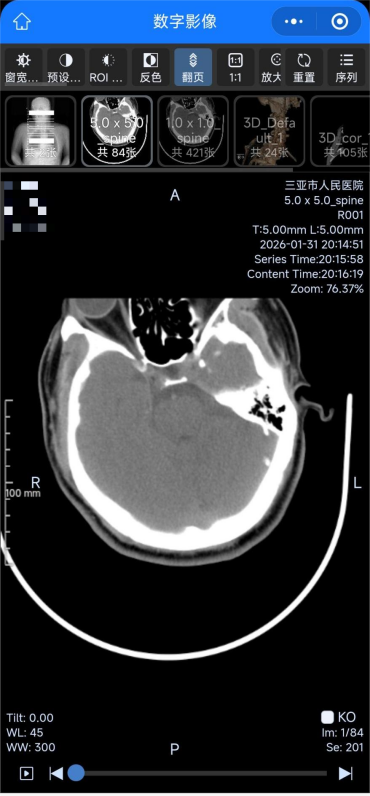

此次升级后,患者在医院完成X线、CT、磁共振等检查,影像数据会实时上传至云端服务器,患者无需在现场等候胶片打印,通过扫描报告单、预约单二维码,或进入医院官方微信公众号,即可在手机、平板等终端便捷调阅、下载、分享完整影像数据及诊断报告。

患者检查后可在手机上查阅高清影像图片。